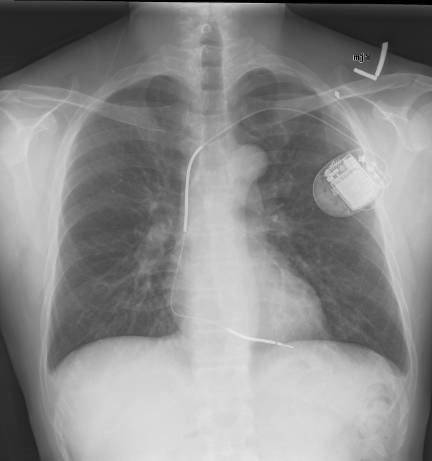

En pacientes con indicación de cardioversor desfibrilador implantable pero sin requerimiento de marcapasos, un dispositivo subcutáneo no fue inferior al desfibrilador transvenoso estándar. New England Journal of Medicine, 6 de agosto de 2020.